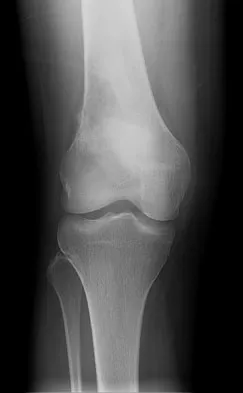

A 28-year-old professional dancer reports a 3-month history of progressive pain in the posterior aspect of the left ankle. Her symptoms are worse when she assumes the en pointe position. Examination reveals tenderness to palpation at the posterolateral aspect of the ankle posterior to the peroneal tendons which is made worse with passive plantar flexion. There is no nodularity, fluctuance, or tenderness of the Achilles tendon. The neurovascular examination is unremarkable. A lateral radiograph and MRI scan are shown in Figures 16a and 16b, respectively. Management should consist of

The imaging studies reveal findings typical of the os trigonum syndrome. This condition results from inflammation between the os trigonum and the adjacent talus. The symptoms of posterior ankle pain are exacerbated by plantar flexion, which stresses the fibrous union between these two bones. Definitive management of the high-level athlete involves excision of the os trigonum from a medial approach, although arthroscopic excision has also been described. The os trigonum is not an intra-articular structure; therefore, ankle arthroscopy is neither diagnostic nor therapeutic. Abramowitz Y, Wollstein R, Barzilay Y, et al: Outcome of resection of a symptomatic os trigonum. J Bone Joint Surg Am 2003;85:1051-1057. Mouhsine E, Crevoisier X, Leyvraz P, et al: Post-traumatic overload or acute syndrome of the os trigonum: A possible cause of posterior ankle impingement. Knee Surg Sports Traumatol Arthrosc 2004;12:250-253.